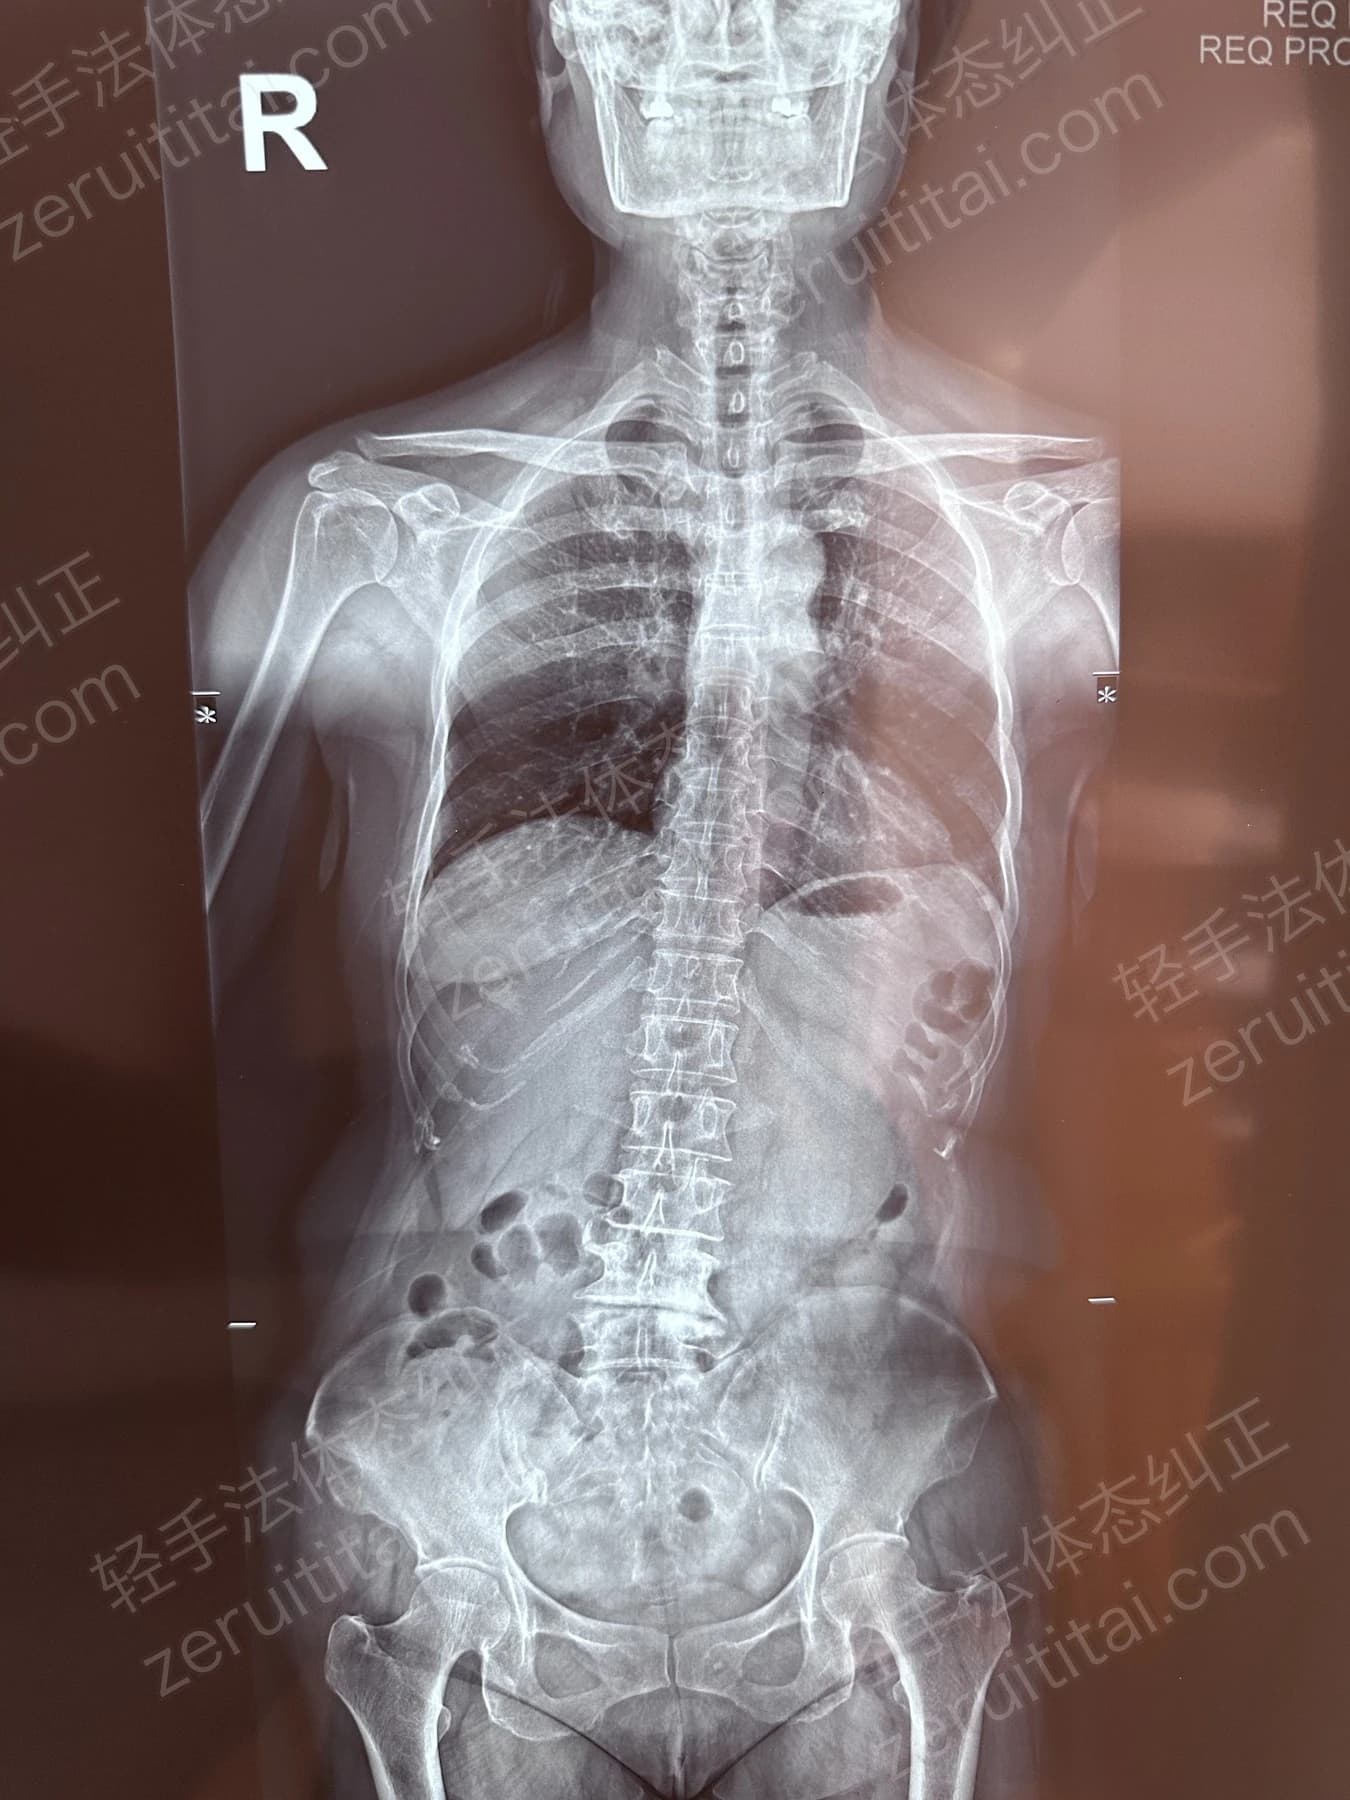

2022.06.27

第 1 次记录